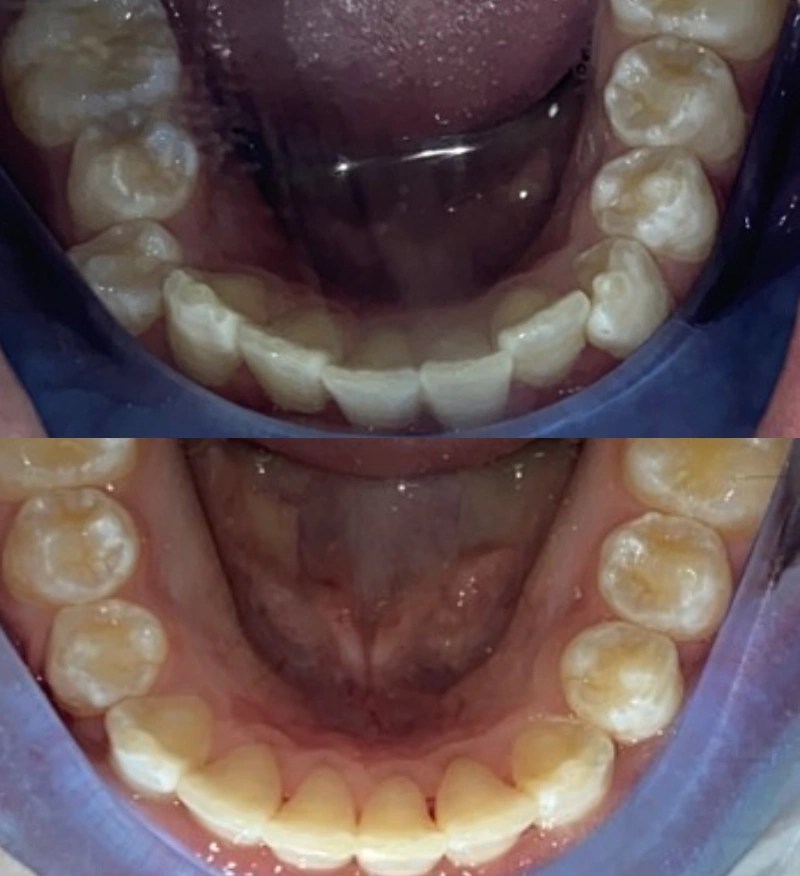

Bottom Tooth Pushed Back / Child Dental Trauma Over the last three Tooth Pushed Back Up Your endodontist or general dentist will reposition and stabilize your tooth. There are many types of dental injuries, including: From what it looks like, he's knocked all top 4 front teeth up into his gums. More severe cases may require a longer recovery time. However, if the underlying cause is more severe, such as advanced gum disease or extensive trauma,. Tooth Pushed Back Up.